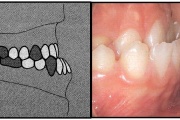

Ravijärgne seis. Jäävhammas on täielikult lõikunud.

) Röntgenülesvõte. Ülemise esimese jäävmolaari lõikumine on takistatud 2. piimamolaari tõttu

Esimese jäävmolaari ektoopiline lõikumine